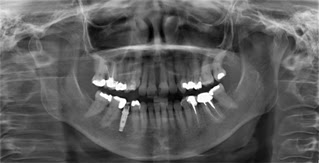

Figura 6. Radiografía panorámica evidenciando necrosis mandibular.

1. Radiografías Panorámicas

Debido al aumento de la población femenina mayor de 50 años de edad en el mundo y la incidencia de fracturas osteoporóticas es necesario detectar pacientes con riesgo de fractura y osteoporosis tempranamente. Esto ha llevado a buscar métodos más costo-efectivos y depurados. Numerosas radiografías panorámicas son tomadas anualmente (aproximadamente 10 millones en Japón, 17 millones en Estados Unidos y 1.5 millones en Inglaterra y Escocia) con el fin de detectar patologías dentales, periodontales y maxilares. (6) Sería beneficioso y económico si estas radiografías pudieran ser utilizadas para identificar mujeres postmenopáusicas con osteoporosis no detectada para que los odontólogos pudieran remitirlas a los médicos para valoración y pruebas de densitometría ósea.

Figura 7. Radiografía panorámica de una paciente diagnosticada con osteoporosis. Se aprecia una disminución del grosor cortical y defectos lacunares reabsortivos.

A continuación menciono los índices reportados en la literatura para analizar cambios de hueso en las radiografías panorámicas.

5.2 Grosor cortical mandibular

Bras y col. fueron los primeros en describir en grosor de la cortical mandibular en el ángulo goniaco como una herramienta útil para evaluar pacientes con enfermedades metabólicas como la osteodistrofia renal. (7) Más adelante, varios investigadores evaluaron si esta medida era efectiva para detectar a los paciente mayores, en especial a las mujeres postmenopáusicas; sin embargo este índice no fue muy bueno ya que la medida en el ángulo es un área muy pequeña, la distorsión horizontal de la radiografía panorámica podría influenciar el resultado, el sitio de medida descrito por Bras y col, no es claro y finalmente, como los músculos maseteros y pterigoideos internos se insertan en el ángulo goniaco, la función oclusal podrían alterar la medición. (6) Por tal motivo se encontró una medida más confiable y validada que consiste en medir el grosor cortical bilateralmente en las radiografías panorámicas en el sitio donde queda el foramen mentoniano. (9) Se traza una línea paralela al eje longitudinal de la mandibular y tangencial al borde inferior de la mandíbula. Una línea perpendicular a esta tangencial, e intersectando el borde inferior del foramen se dibuja, de esta manera se mide con una regla el grosor y se promedia usando las dos medidas. (10)

Figura 8: Medición del grosor de la cortical

5.3 Forma de la cortical mandibular:

El método de Klemetti et al. en 1994, es un índice validado que describe la morfología cortical de la siguiente manera(8),

Figura 9. Diferencias cualitativas de la cortical mandibular entre un paciente sano a otro con osteoporosis.

La radiografía panorámica es una herramienta útil para detectar pacientes con factores de riesgo asociados a osteoporosis y fracturas por fragilidad no diagnosticados y poder encaminarlos adecuadamente.